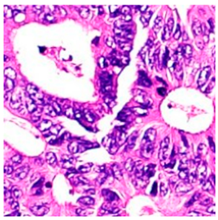

3.6. Visualizing Interpretability in CRC Classification Using ADFMs

| Tissue Class | Original Image | Heatmaps | Superimposed Image |

|  |  |  |

|  |  |  |

|  |  |  |

|  |  |  |